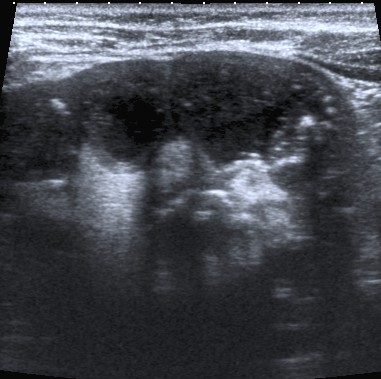

Ecografía:

- Agrandamiento y distorsión de la silueta renal.

- Pérdida difusa de la arquitectura renal normal.

- Gran ecogenicidad central amorfa que corresponde a un cálculo coraliforme en la pelvis renal.

Aunque estos hallazgos son más carácteristicos, se realiza posteriormente una TC para mejor valoración.

Paciente mujer de 62 años que acude por decaimiento general con fiebre y dolor en flanco izquierdo. Ingresa en UVI por signos de sepsis

Nos cuenta antecedentes de pielonefritis e hidronefrosis crónica.

Hallazgos en imagen:

Estos hallazgos pueden ser dificiles de interpretar, ya que una paciente con hidronefrosis crónica y litiasis en el uréter puede haber sufrido una obstrucción que origina un cuadro de dolor en FRI con ruptura de cálices y colección extra axial. Otra probabilidad puede ser un angiomiolipoma que ha roto un aneurisma y ha producido un sangrado. También podríamos estar ante una pionefrosis aunque dada dada la clínica, los antecedentes y al observar los hallazgos en TC podríamos establecer la sospecha de pielonefritis xantunogranulomatosa con alta probabilidad. La confrimación vendrá dada con la nefrostomía y estudio de anatomía patológica.